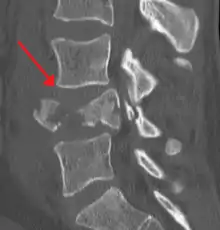

كسور الفقرات الظهرية والقطنية

عدم الاستقرار المزمن لبنية العمود الفقري

أكثر الأمثلة شيوعاً التي من الممكن أن تؤثر على الاستقرار الهيكلي للفقرات هي الانزلاقات الغضروفية المزمنة، وانحلال أو انزلاق الفقار، والتضيق الشوكي، والحداب مثل داء شورمان، والجنف. كما أنه يمكن أن تعتبر الأورام أو التهابات من الأسباب المزمنة لعدم الاستقرار إذا بقيت لفترات زمنية طويلة.[2]